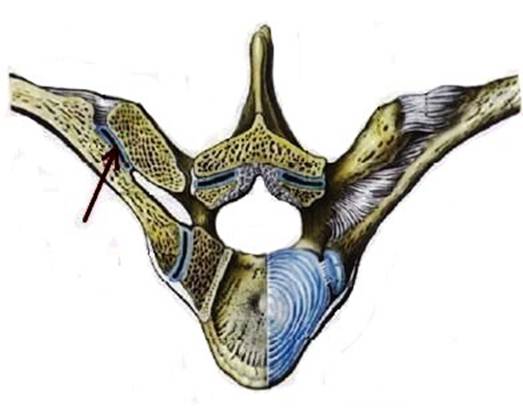

S: Стрелка указывает на art. Costotransversaria

S: Стрелка указывает на art. Capitis costae

S: Стрелками выделен art…